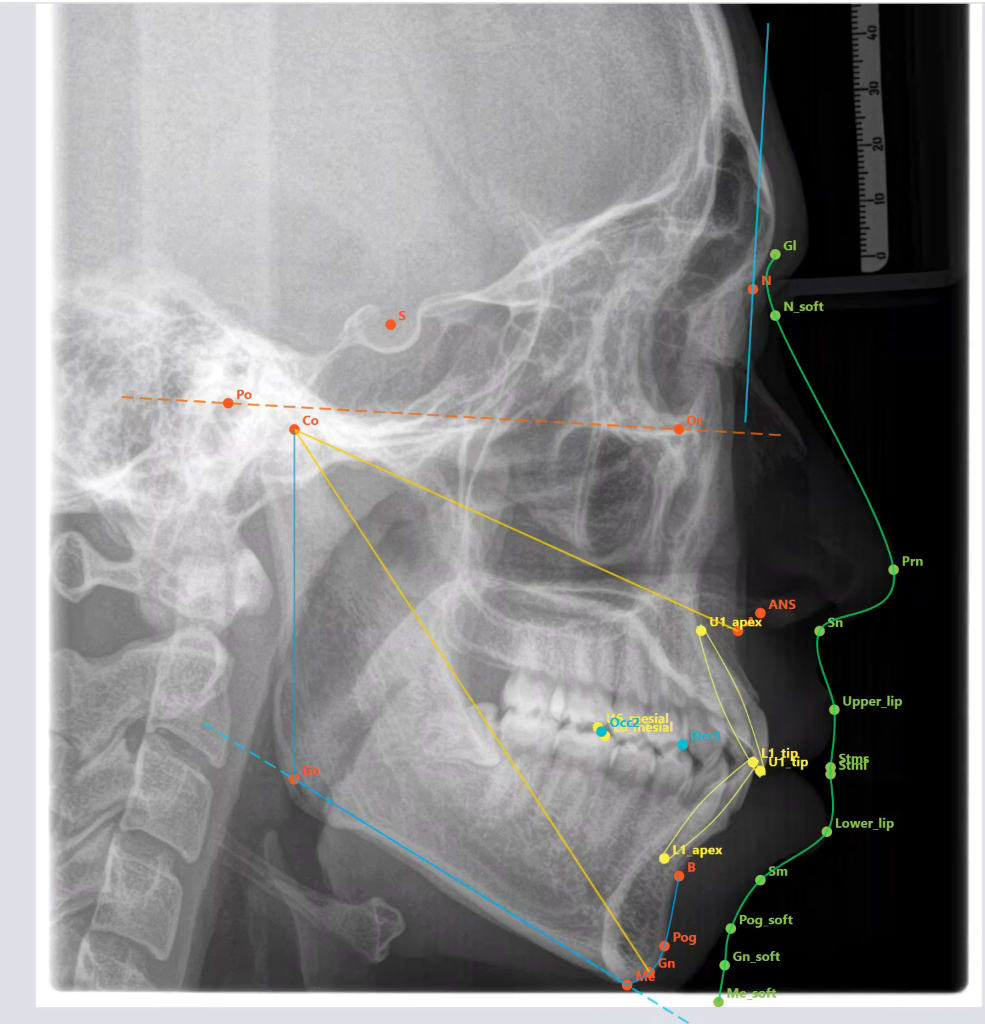

Et detection des points par IA rajouté.

J'ai due entrainer l'IA en locale sur mon PC , ça à prit quelque heure mais le résultat est impressionnant. Les points s'affiche en moins d'une seconde..

La détections des points se fait un moins d'une seconde.

J'ai entrainer un réseau neuronaux à reconnaitre les points avec du matériel d'entrainement en ligne. Tout est dans le soft ( environ 150 MB) pas besoin d'être connecté à internet pour que ça marche.

La je suis en train d'améliorer la détection des lignes du visage. Après il va falloir tester sur plusieurs ordi et fin de la semaine prochaine on met en ligne :-)

Quand j'ai vérifier la littérature sur le sujet il y a deux mois, les points ne sont jamais parfaitement placé :-) . Ca confirme mon expérience avec webceph. Il y en a toujours un ou deux à bouger un peut. Pour des raisons technique et légale tu auras toujours besoin de revoir la position des points.

Avec mon soft c'est la même chose, l'idée c'est plus de faire gagner du temps sur le combo placé les points + tracés .

La détection automatique marche bien. Il faut rajouter quelque point sauf McNamara ( la photo c'est juste après avoir cliqué auto détecté et attendue une seconde). J'ai rajouté l'option d'exporter les fichiers patient/radio/analyse . Il y a toujours des points à déplacer et le tracer du visage pourrait être amélioré mais pour une premier soft réalisé en solo en quelque jours c'est déjà pas mal :-)

Maintenant c'est juste du débuggage puis on va envoyer au beta testeur et l'on distribue en libre la semaine prochaine.